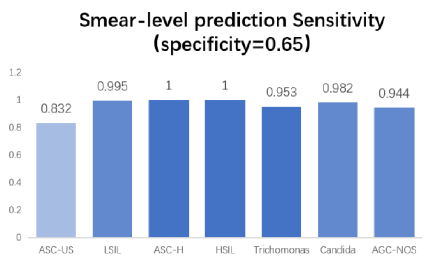

High sensitivity validated in clinical

practice for different lesion types

Graded lesion cells, count cell quantity

automatically

Whole-slide analysis, high TPR, slide

quality intelligent assessment

Built-in error correction feedback system,

periodically update algorithm